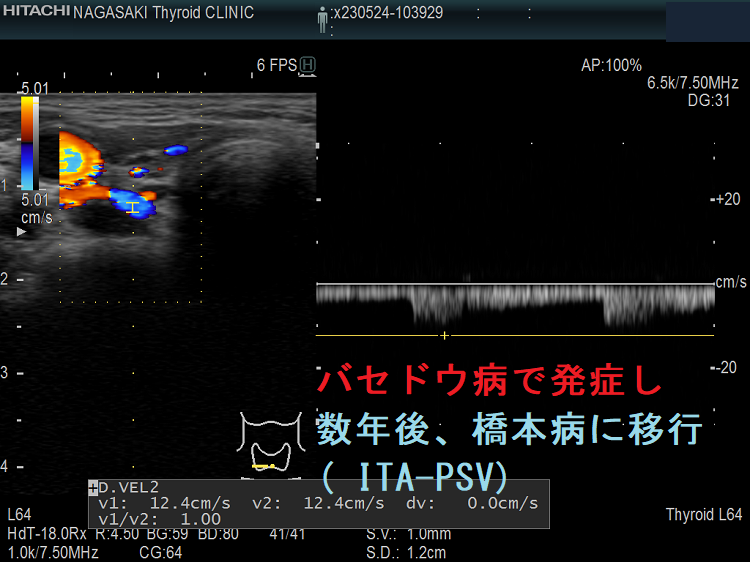

橋本病とバセドウ病は、全くの別物ではありません。それどころか、根本は同じで、時としてバセドウ病から橋本病に、バセドウ病から橋本病に移行する事が多々あります。[Endocrine. 2023 Dec 20. doi: 10.1007/s12020-023-03634-x.][Cureus. 2024 Jan 19;16(1):e52598.]

例えば、甲状腺機能亢進症/バセドウ病で、メルカゾールなど甲状腺ホルモンを下げる薬が必要なくなり、その後、橋本病に移行。甲状腺機能低下症/橋本病で、甲状腺ホルモン剤(チラーヂンS)が必要なくなり、甲状腺機能亢進症/バセドウ病に変わったりします。

よくあるパターンは「若い時、バセドウ。齢(とし)いって橋本」と言うやつです。(当然、逆もあり)